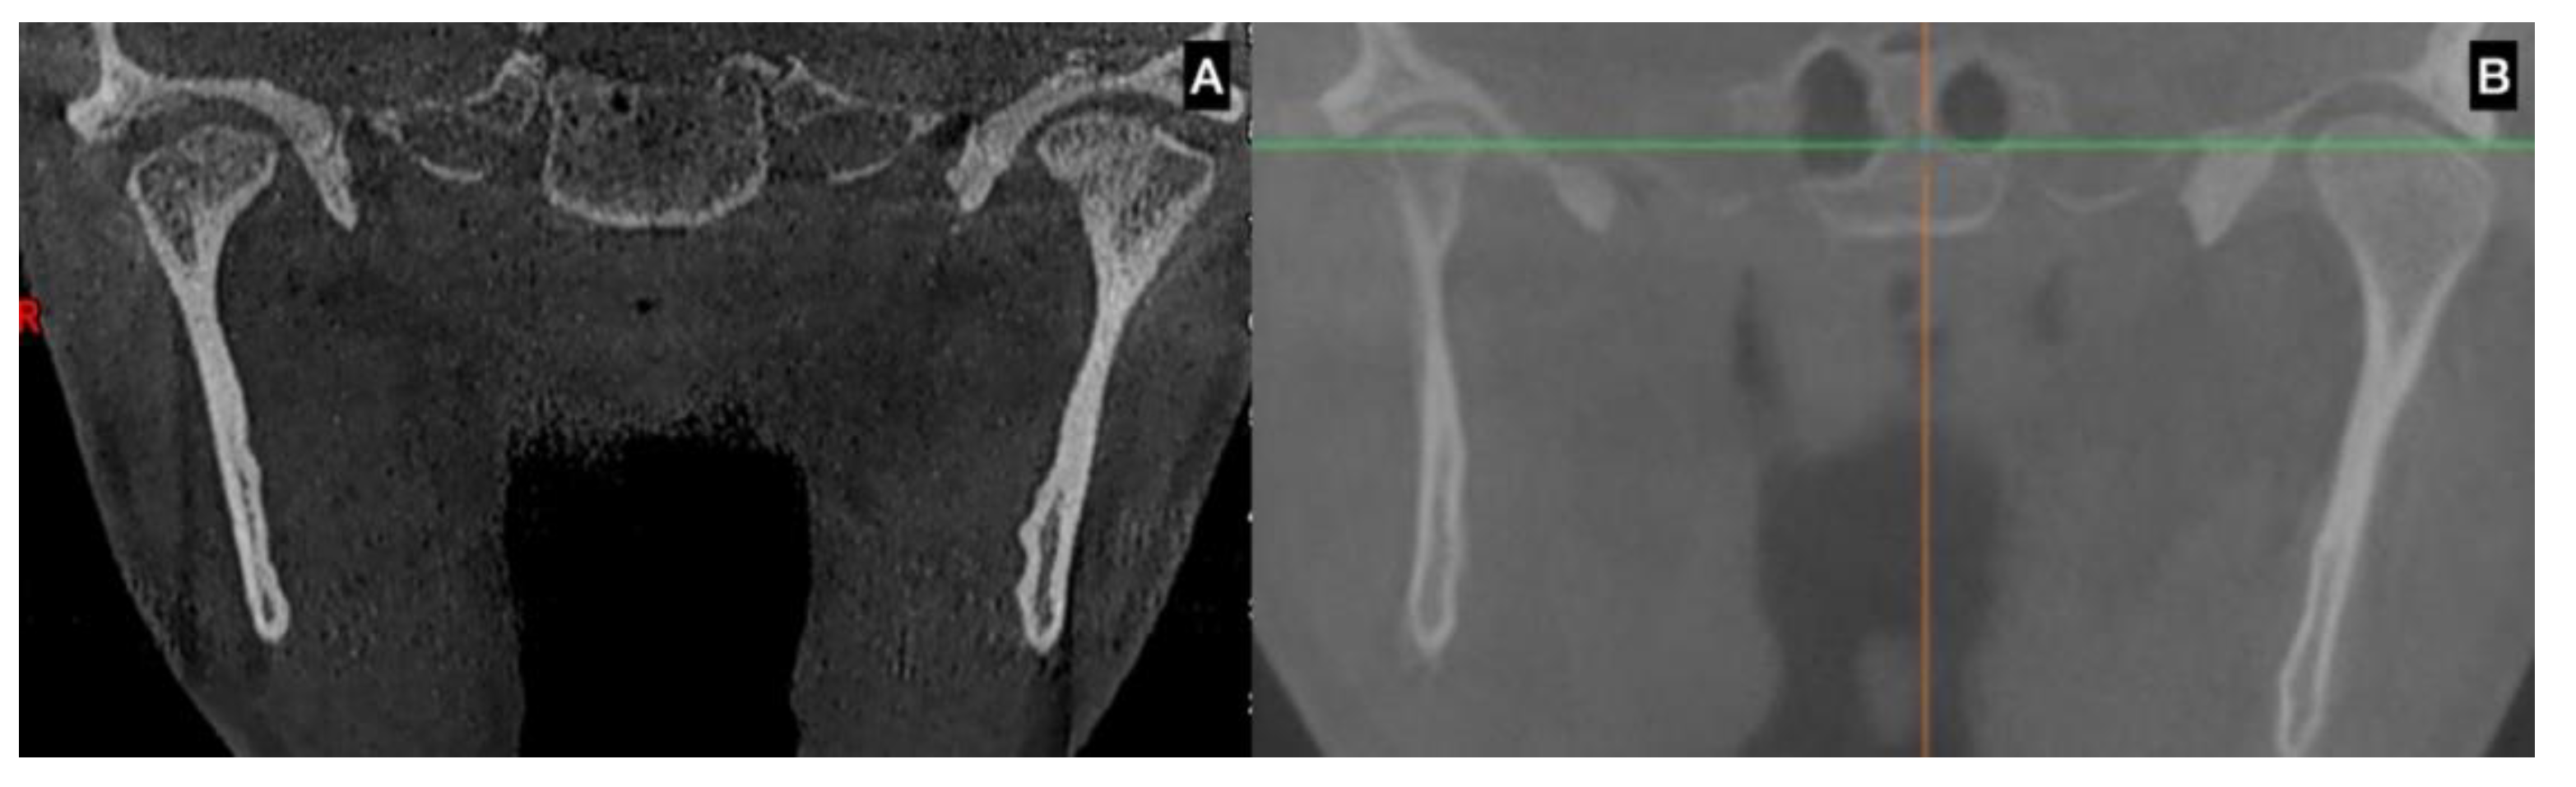

| CBCT | Augmentation in condylar size in comparison to the non-hyperplastic condyle |

| Lack in upper cortical line of the affected condyle in the upper area showing an active metabolism | |

| Augmentation in radiolucency in the affected condyle with an image related to poor density in some cases | |